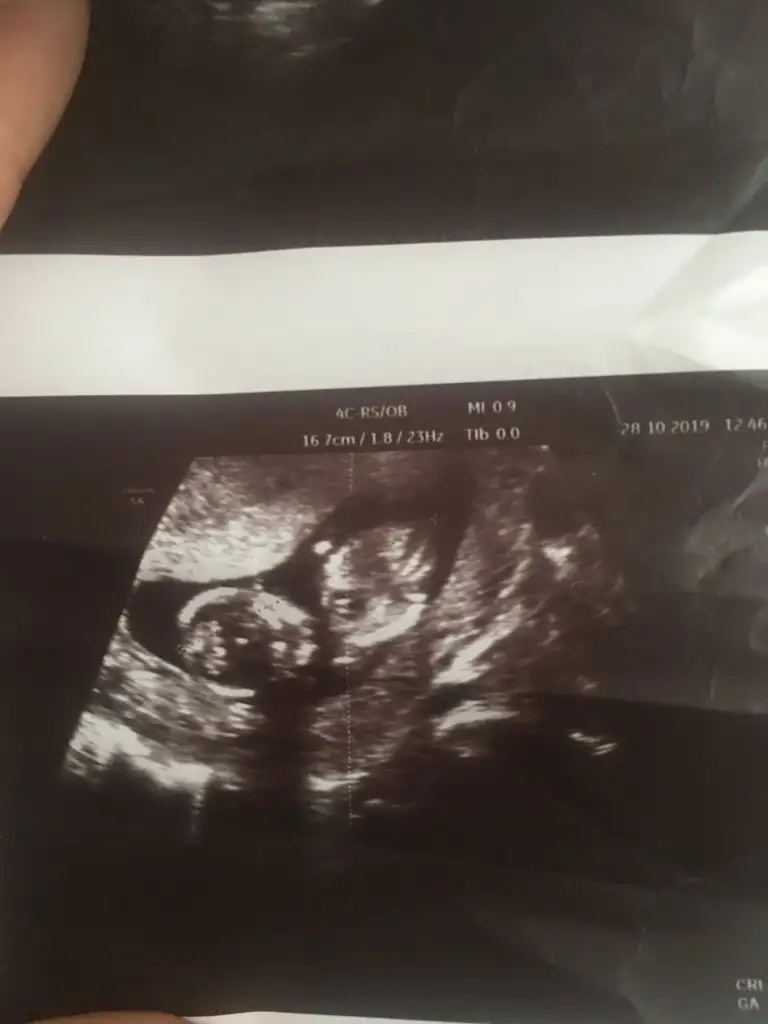

var.Erkek benceMerhabaIkra meyra rica etsem bir tahmin yapabilir misin bana da? Burda 11+ 5 haftalık USG resmiEki Görüntüle 2549567 var.

KızMerhabaIkra meyra rica etsem bir tahmin yapabilir misin bana da? Burda 11+ 5 haftalık USG resmiEki Görüntüle 2549567 var.

14 hafta görünüyorsunuz dr tahmin etmedimiTeşekkürler

Kontrolüm 2 hafta sonra 15+ 5 te. 11+5 te yüzde 60 kız dedi14 hafta görünüyorsunuz dr tahmin etmedimi